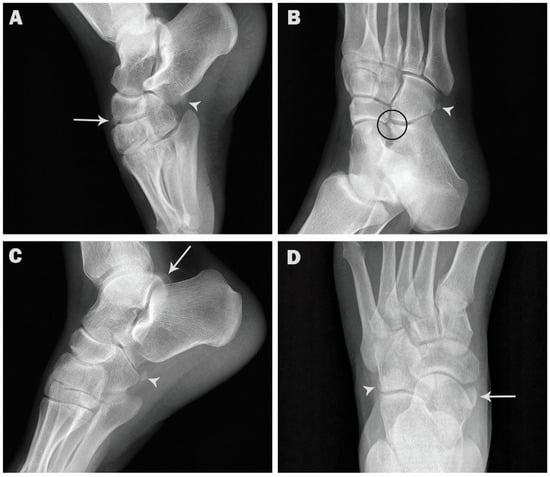

| Os intermetatarseum | 2 (0.2) | 1 (0.2) | 1 (0.2) | 2 (0.3) | 0 (0) |

| p value | 1.000 ns | 1.000 ns | |||

| Os supratalare | 3 (0.3) | 2 (0.4) | 1 (0.2) | 1 (0.1) | 2 (0.6) |

| p value | 1.000 ns | 0.2493 ns | |||

| Os supranaviculare | 7 (0.7) | 6 (1.2) | 1 (0.2) | 4 (0.6) | 3 (0.9) |

| p value | 0.1237 ns | 0.6886 ns | |||

| Os talotibiale | 4 (0.4) | 3 (0.6) | 1 (0.2) | 2 (0.3) | 2 (0.6) |

| p value | 0.6242 ns | 0.6001 ns | |||